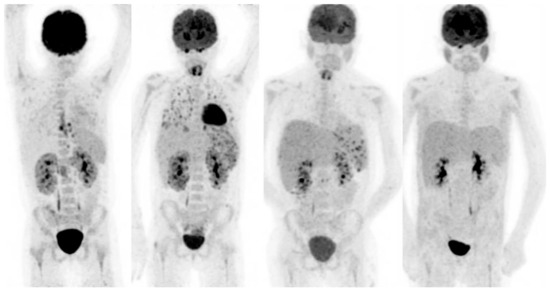

- Martìnez-Rodrìguez, I.; Jiménez-Alonso, M.; Quirce, R.; Jiménez-Bonilla, J.; Martìnez-Amador, N.; De Arcocha-Torres, M.; Loricera, J.; Blanco, R.; González-Gay, M.Á.; Banzo, I. 18F-FDG PET/CT in the follow-up of large-vessel vasculitis: A study of 37 consecutive patients. Semin. Arthritis Rheum. 2018, 47, 530–537. [Google Scholar] [CrossRef] [PubMed]

- Karunanithi, S.; Sharma, P.; Bal, C.; Kumar, R. (18)F-FDG PET/CT for diagnosis and treatment response evaluation in large vessel vasculitis. Eur. J. Nucl. Med. Mol. Imaging 2014, 41, 586–587. [Google Scholar] [CrossRef]

- Muto, G.; Yamashita, H.; Takahashi, Y.; Miyata, Y.; Morooka, M.; Minamimoto, R.; Kubota, K.; Kaneko, H.; Kano, T.; Mimori, A. Large vessel vasculitis in elderly patients: Early diagnosis and steroid-response evaluation with FDG-PET/CT and contrast-enhanced CT. Rheumatol. Int. 2014, 34, 1545–1554. [Google Scholar] [CrossRef]

- Henes, J.C.; Mueller, M.; Pfannenberg, C.; Kanz, L.; Koetter, I. Cyclophosphamide for large vessel vasculitis: Assessment of response by PET/CT. Clin. Exp. Rheumatol. 2011, 29, S43–S48. [Google Scholar]

- Salvarani, C.; Magnani, L.; Catanoso, M.; Pipitone, N.; Versari, A.; Dardani, L.; Pulsatelli, L.; Meliconi, R.; Boiardi, L. Tocilizumab: A novel therapy for patients with large-vessel vasculitis. Rheumatology 2012, 51, 151–156. [Google Scholar] [CrossRef]